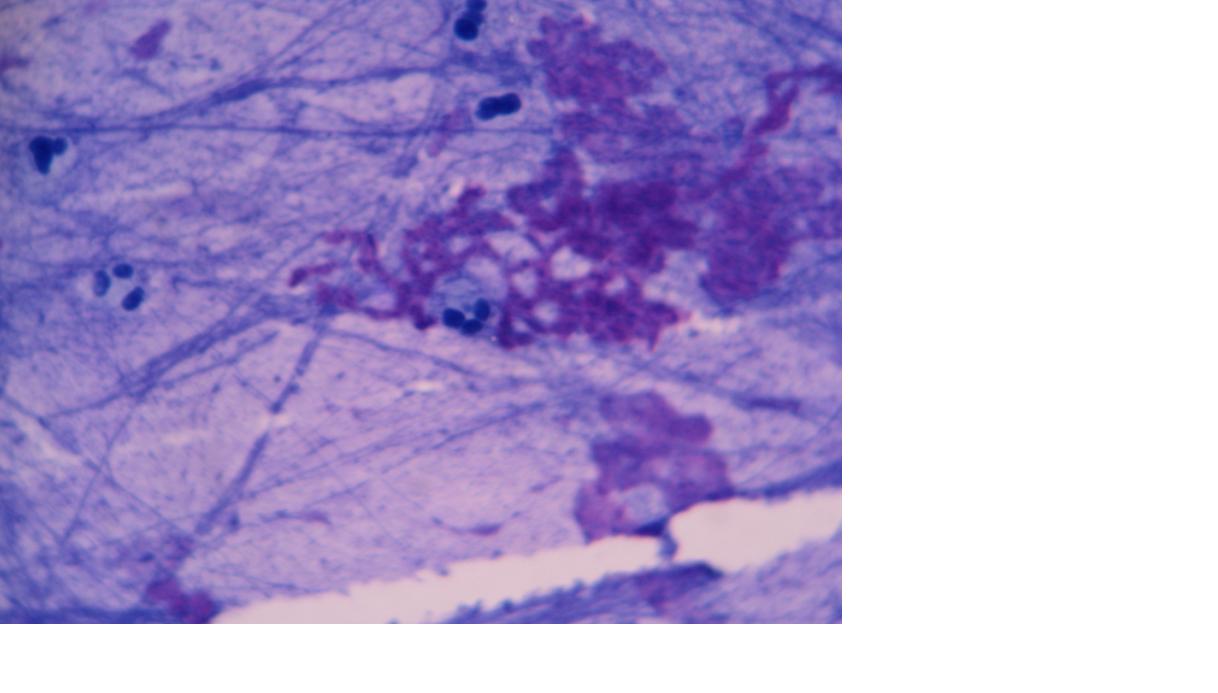

铜绿生物膜2.jpg 铜绿生物膜3.jpg 铜绿生物膜4.jpg

上面发的图片均是来自一株粘液型铜绿形成的生物膜,虽然胞外结构非常厚重,但是细菌的模样还是能勉强辨认出看来的。

由于该菌产生的藻酸盐粘液质具有弱抗酸性,为了突出生物膜,所以这里都是采用抗酸染色的。